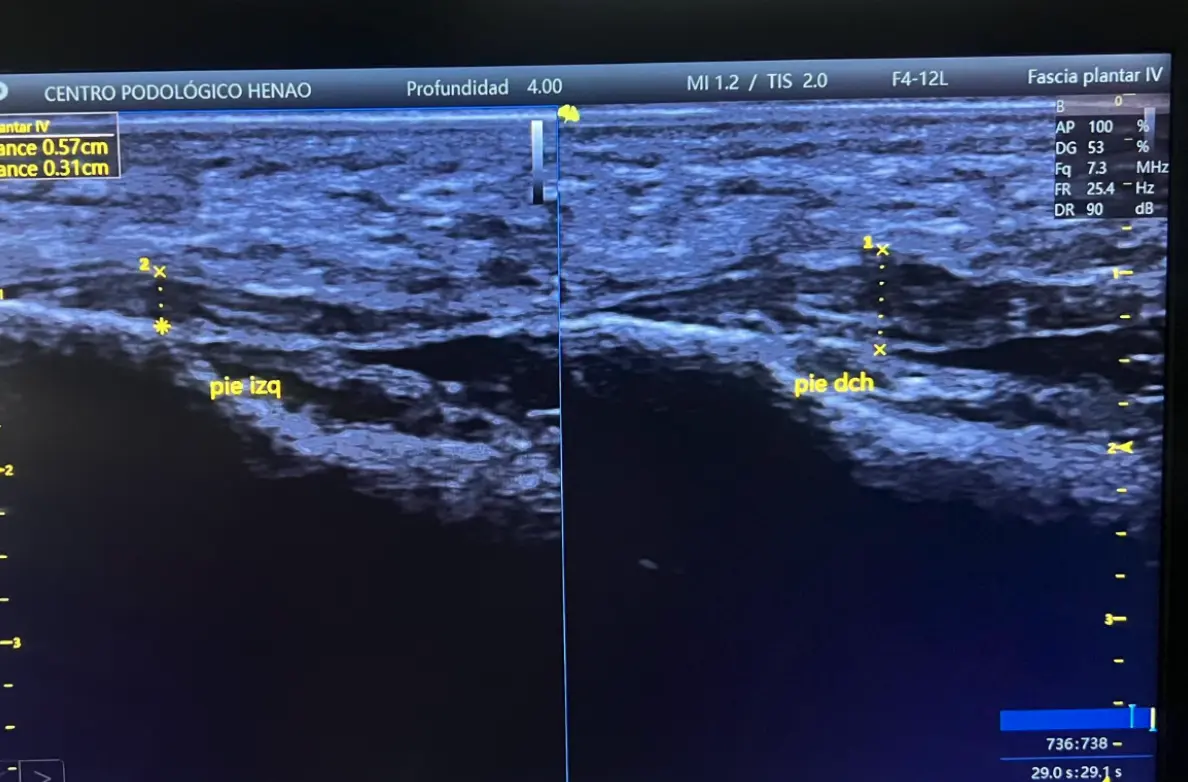

- Ecografía: Engrosamiento de la fascia plantar (5.2 mm, normal < 4 mm)